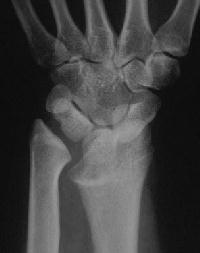

Madelung's deformity is a dysplasia of the radius resulting in an exaggerated radial inclination, a short forearm, dorsal dislocation of the ulnar head and a "V" shaped proximal carpal row. It may be painful and may result in extensor tendon rupture. Congenital Madelungs may be due to an abnormal fibrous band tethering sigmoid notch of the radius proximally to the ulna. Traumatic Madelung's may follow partial growth arrest of the distal radius. Treatment options differ in the mature and immature skeleton.

Case 1. Typical Xray findings of congenital Madelungs.